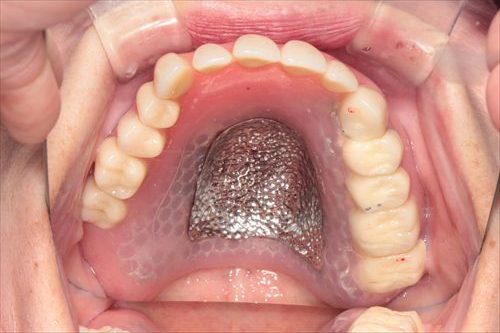

義歯を外したところです。

上下どちらの顎も、歯の無い部分が大きくえぐれているのがわかるでしょうか?

これがすれ違い咬合の怖さです。残っている歯による顎の骨への攻撃が強いため、顎の骨が経年的に失われていきます。